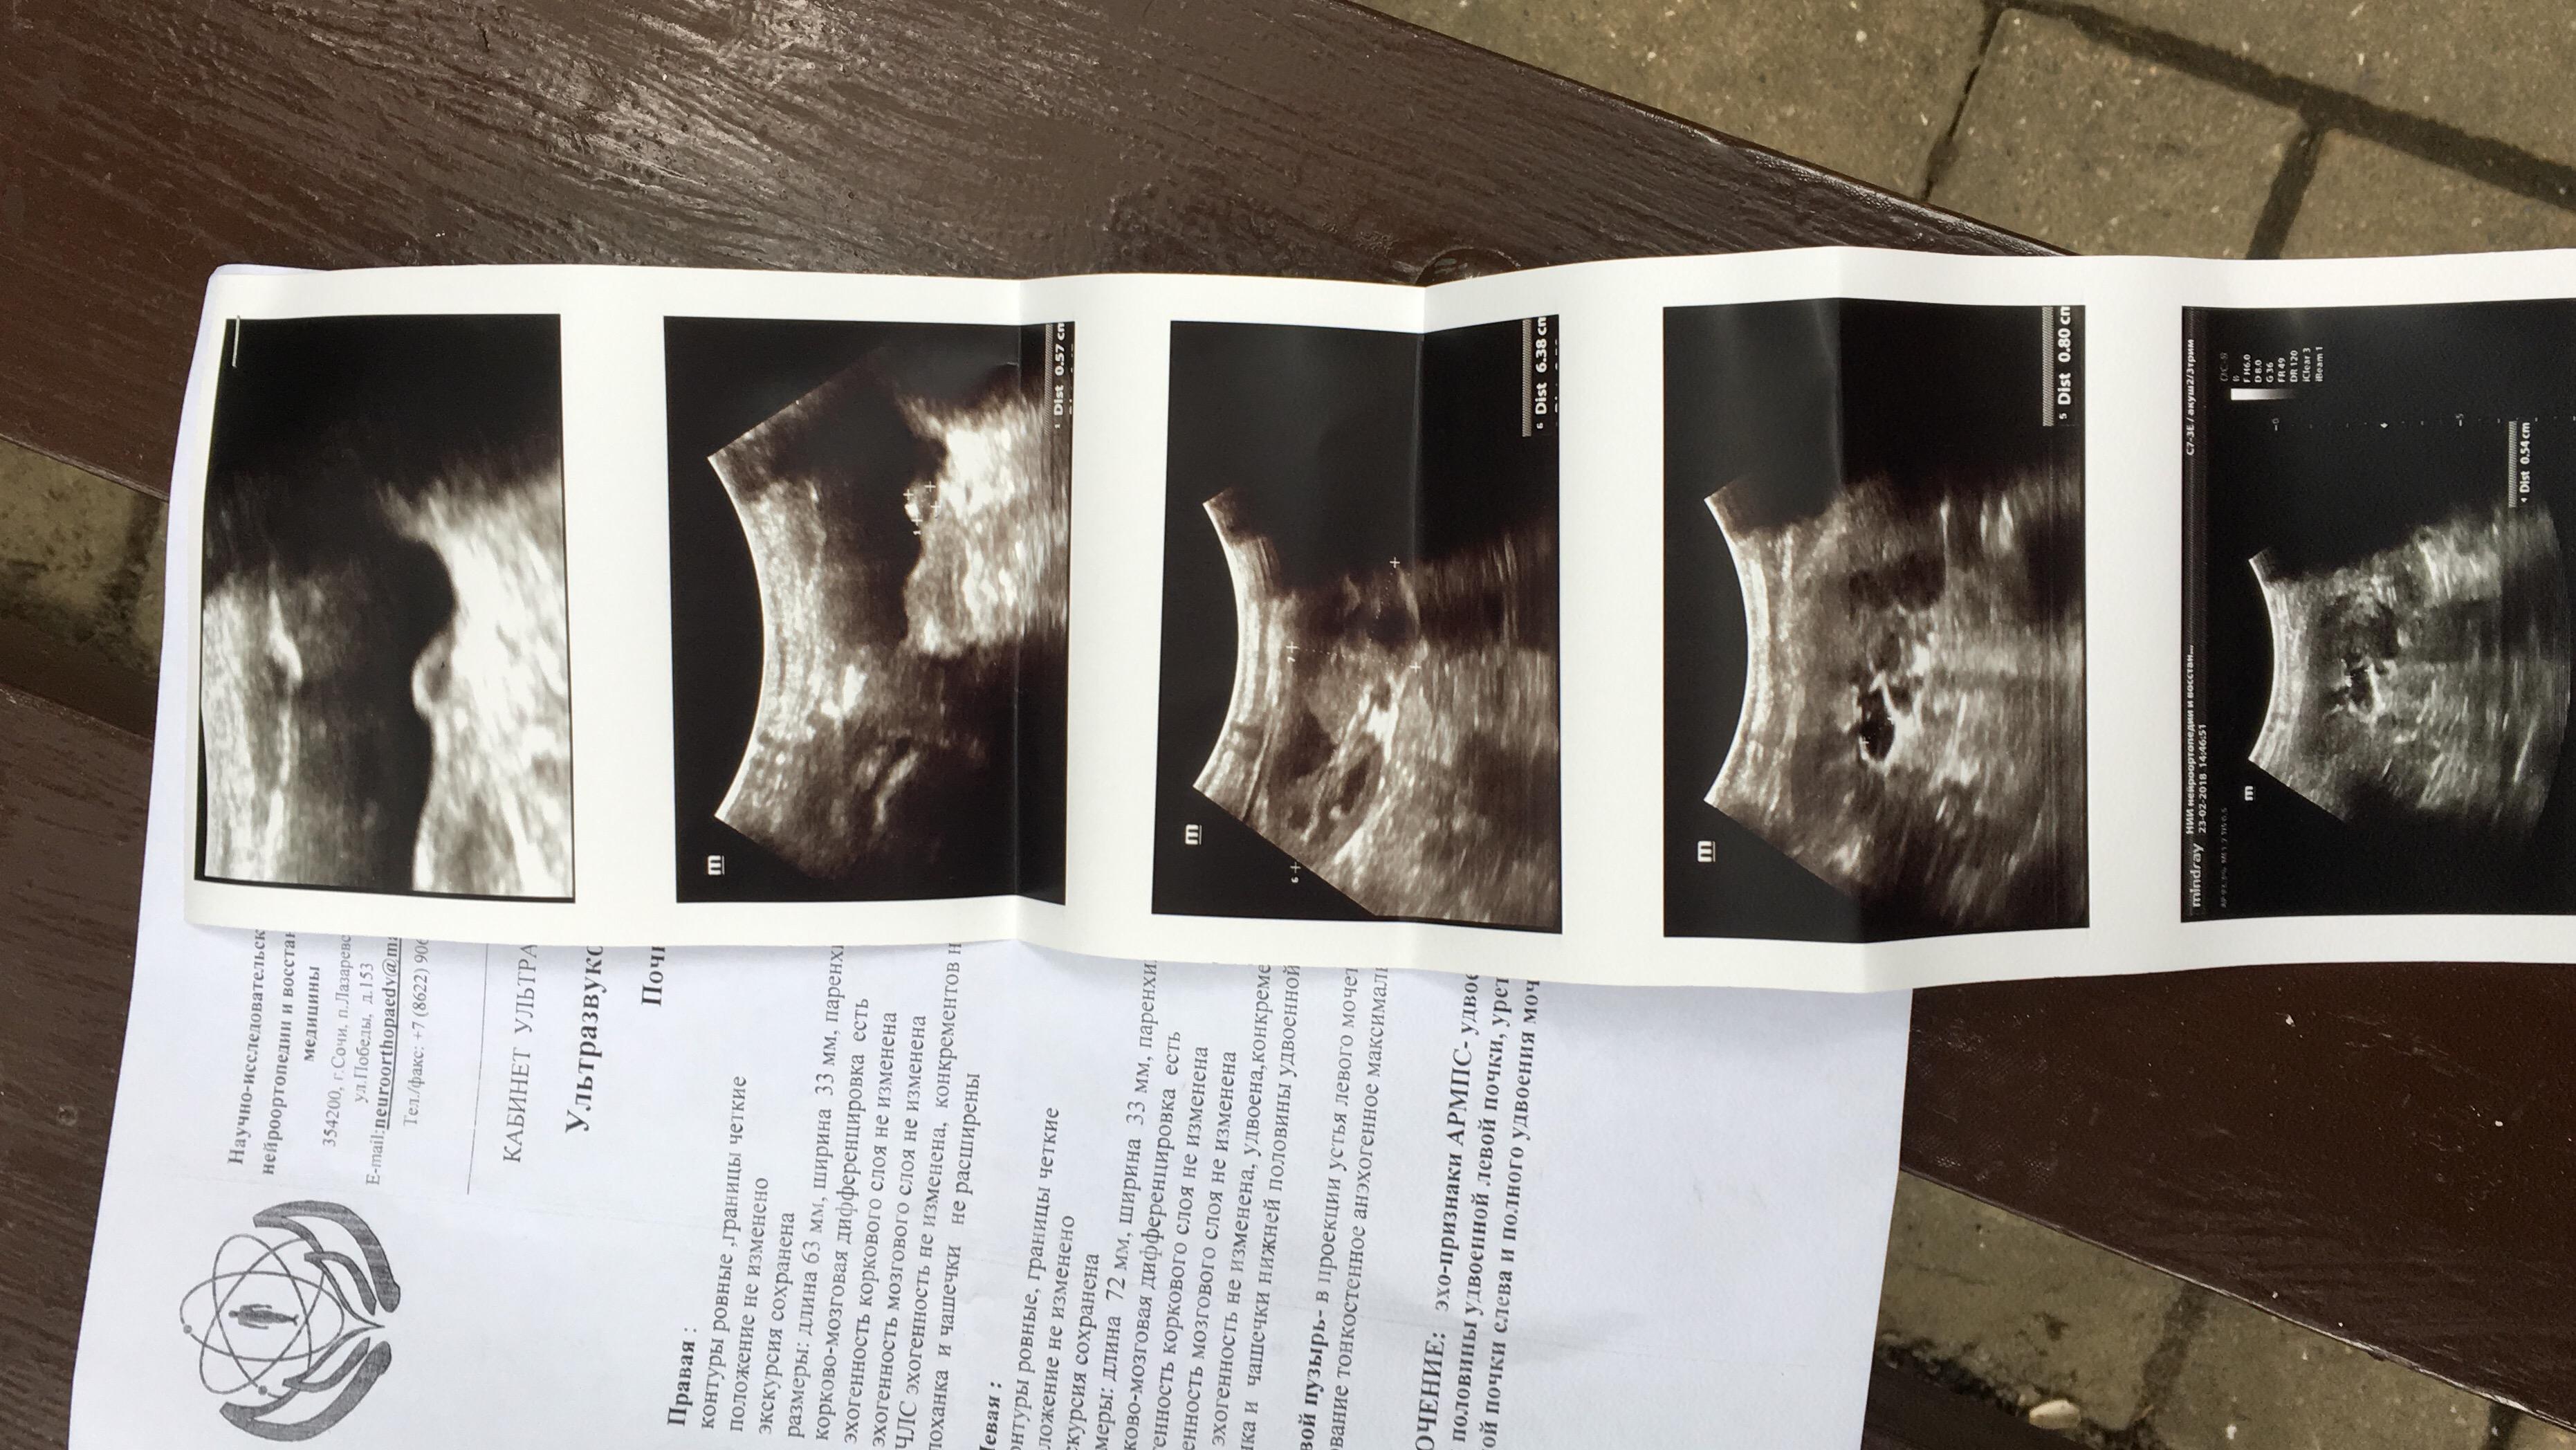

Здравствуйте, у ребёнка в месяц сделали Узи в заключении написали пилокаликоэктозия почки и каликоэктазия почки, сдаём мочу. В три месяца делаем контроль, (в поликлинике) уже они не видят эктозий, видят удвоенную почку.так же сдаём мочу, вроде все нормально. Далее в 11 месяцев сдаю мочу, а там лейкоциты 25, белок 0,066. В детском отд делают цефтреаксон, пьём канефрон, делают Узи и пишут удвоенная почка и косвенные признаки пиелонефрита. Пошли к платному урологу на хорошее Узи прилагаю заключение. Что нам делать с таким диагнозом? Нужна ли операция? Если нужна, то с какого возраста делают такие операции?